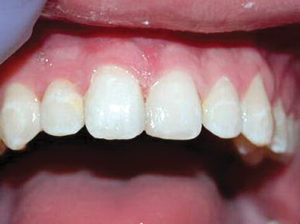

Caso 1

Un paciente de 8 años presentó descomposición de OD en un primer molar primario con síntomas de pulpitis reversible. El diente fue el tratamiento planificado para una restauración de OD con Activa Bioactive Restorative (Pulpdent). Tras la excavación por descomposición, se produjo una exposición pulpar que requirió una pulpotomía terapéutica. Debido a la edad del paciente, me sentí cómodo con una pulpotomía terapéutica con Biodentine (Septodont) seguida de una restauración estética. Si el paciente hubiera tenido entre cuatro y cinco años, me habría restaurado con una corona de acero inoxidable debido a su historial comprobado de longevidad.

Figura 1 Vista preoperatoria del primer molar primario superior. |